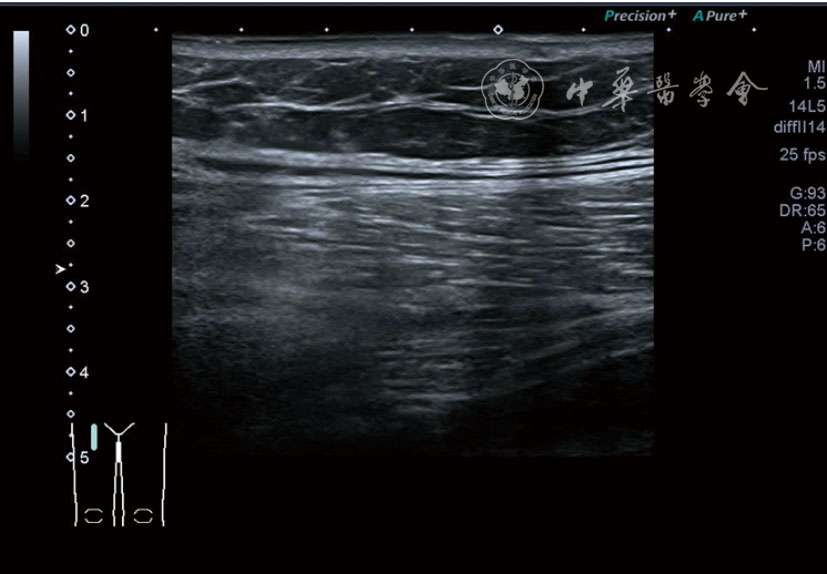

3.膝关节内局部治疗。随着病情发展,静态结构失衡,膝关节内部结构发生变化,会出现软骨损伤、脱落,关节间隙变窄,内外间隙不等,骨赘形成等。膝关节内局部治疗包括关节内症状性骨赘剥离、玻璃酸钠及PRP注射等。(1)膝关节内症状性骨赘针刀剥离松解治疗。由于软骨缺损或者力平衡失调,在关节内脱落软骨区会出现骨赘。部分骨赘引起疼痛,或者与髌骨撞击出现临床症状需要治疗。针刀剥离目的不是去除骨赘,而是剥离松解,缓解或者消除疼痛。以股骨外髁骨赘为例。患者平卧位,膝关节屈曲100°~120°。一般选用10 MHz超声探头,穿刺区域常规消毒,探头涂抹耦合剂后套入无菌手套碘伏消毒或使用无菌耦合剂。将探头置于患者皮肤表面,短轴扫查,显示关节面与骨赘,选用25G注射针,抽吸1%利多卡因3 ml于骨赘周围进行分层麻醉。选用直径1 mm的Ⅰ型2号针刀,在超声引导下从外侧向内侧到达骨赘,反复剥离,一般5~8刀后拔出针刀结束治疗(图18),局部压迫5分钟,无菌敷料覆盖。(2)膝关节髌上囊积液治疗。髌上囊积液在膝关节骨关节炎比较常见,尽管积液量可能很大,但通过软组织松解治疗后,大部分患者积液会减少或者消失。所以积液的治疗可以放在后面处理。超声引导下抽出积液,药物注射是常用的治疗方法。膝关节炎积液的治疗通常包括关节内皮质类固醇激素或者臭氧注射。如果慢性以滑膜丛型增生为主,针刀有限切割增生滑膜加药物注射可提高疗效。①髌上囊积液抽吸加臭氧注射治疗。患者平卧位,膝关节屈曲30°~60°,膝下垫一软枕。选用10 MHz超声探头,治疗前消毒准备同骨赘针刀剥离松解治疗。将探头置于患者皮肤表面,短轴扫查,找到积液最多处,应用22G针头,直接穿刺进入髌上囊抽出液体,然后根据髌上囊大小制备35 μg/L的15~20 ml臭氧注入髌上囊内拔出针头(图19),局部压迫2分钟,无菌敷料覆盖。②髌上囊慢性滑膜炎针刀切割松解治疗。患者平卧位,膝关节屈曲30°~60°,膝下垫一软枕。选用10 MHz超声探头,治疗前消毒准备同骨赘针刀剥离松解治疗。将探头置于患者皮肤表面,长轴或短轴扫查,找到积液最多处,用一次性5 ml注射器抽吸1%利多卡因3 ml于髌上囊进行分层注射麻醉,囊内也要注射适量麻药,尽量抽出积液。选用直径1 mm的Ⅰ型2号针刀,长轴扫查从近端向远端,短轴扫查从外侧向内侧,在超声引导下进入囊肿内对内壁及增生滑膜的不同方向、角度进行反复切割(图20),一般2~3分钟拔出针刀,然后囊内注射1%利多卡因3 ml+曲安奈德15 mg,结束治疗,局部压迫5分钟,无菌敷料覆盖。(3)膝关节腔PRP注射治疗。关节腔注射主要是为了修复软骨,如果不是为了治疗积液,不主张应用激素类药物。目前主要的注射药物为玻璃酸钠、PRP。按照传统的注射部位,多为髌上内、外或者髌下内、外注射点,但是超声不能观察到注射针的位置,药物也不能很好到达软骨损伤的部位,效果受到影响(图21)。膝关节软骨损伤的主要部位在髌股关节的股骨髁,超声可以很好地显示这一部位,并能显示软骨变薄。因此,由这个路径平面内进针注射,可以很好显示穿刺针的路径与位置。以注射PRP为例。患者平卧位,膝关节屈曲100°~120°,选用10 MHz超声探头,治疗前消毒准备同骨赘针刀剥离松解治疗。将探头置于患者皮肤表面,短轴扫查显示关节面,应用25G注射针头,抽吸1%利多卡因2 ml由内侧进针进行分层麻醉直达关节软骨面。制备4.5 ml PRP,直接注射到关节面,液体顺关节面分布,注射完毕拔出针头(图22)。局部压迫2分钟,无菌敷料覆盖。(4)髌骨软化超声影像融合技术下PRP注射治疗。髌骨软化是指髌骨关节面的软骨损伤,软骨下骨囊变,MRI能够明确诊断,但是超声不能显示。应用超声与MRI的影像融合技术,依据MRI明确注射部位,在超声引导下可将药物精准注射到软骨损伤的部位。患者平卧位,膝关节屈曲30°,下面垫一软枕。一般选用10 MHz超声探头,治疗前消毒准备同骨赘针刀剥离松解治疗。将MRI的原始图像数据导入超声设备中,进行手动影像融合,完全融合后,确定穿刺靶点,以MRI图像为目标,以超声图像为实时引导进行穿刺,到达目标后,注射提前制取的PRP 3 ml(图23),注射完毕拔出针头,局部压迫3分钟,创可贴覆盖。

图20 超声引导下髌上囊慢性滑膜炎针刀切割松解治疗